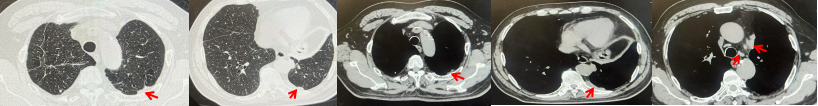

2024.11.19患者出现右侧胸痛,复查胸部CT检查示右侧胸膜肿物,大小约31mmX24mm,右侧4、5肋骨骨质破坏,考虑转移(如图2)。建议患者穿刺活检取病理明确诊断,患者拒绝,经MDT会诊后结合影像学表现及病史考虑为胸膜转移,肋骨转移,分期为rT0N0M1a IVA期,DFS仅仅17个月。2024.12.05起行信迪利单抗联合培美曲塞+卡铂方案治疗4周期,复查胸CT评效PR(如图3)。之后给予信迪利单抗+培美曲塞维持治疗6周期,期间复查CT评效PR(如图3)。目前信迪利单抗+培美曲塞维持治疗中,截止至目前PFS约为8个月,治疗期间未出现明显毒副反应。

图2:患者胸膜及肋骨转移(2024.11)胸部CT肺窗、纵隔窗及骨窗